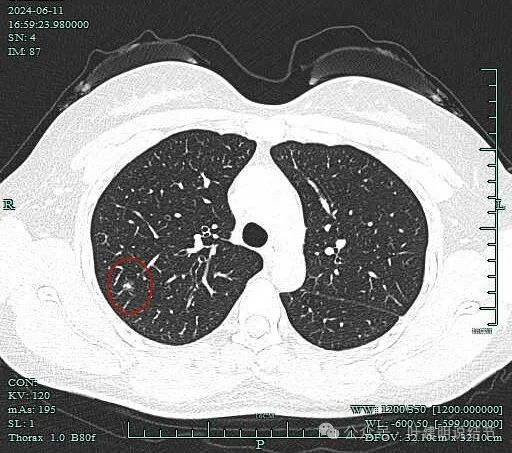

先看2024年6月的影像:

病灶出现,磨玻璃密度,似乎伴小空泡的样子,整体轮廓较清。